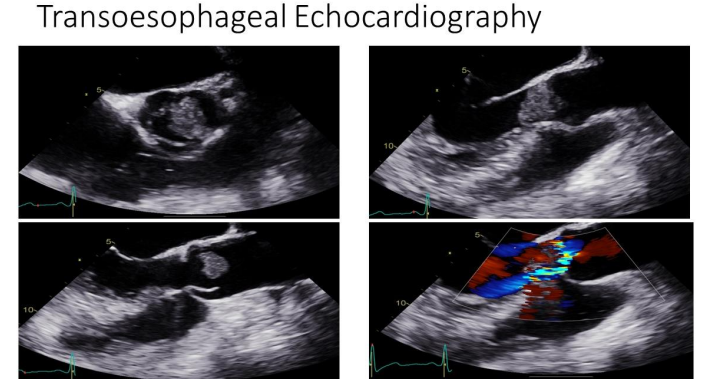

Echocardiography

A transthoracic echocardiogram, conducted as part of her routine stroke workup, revealed:

• A large aortic valve mass

• Moderate eccentric aortic regurgitation

• Absence of left ventricular outflow tract (LVOT) obstruction

Figure 1